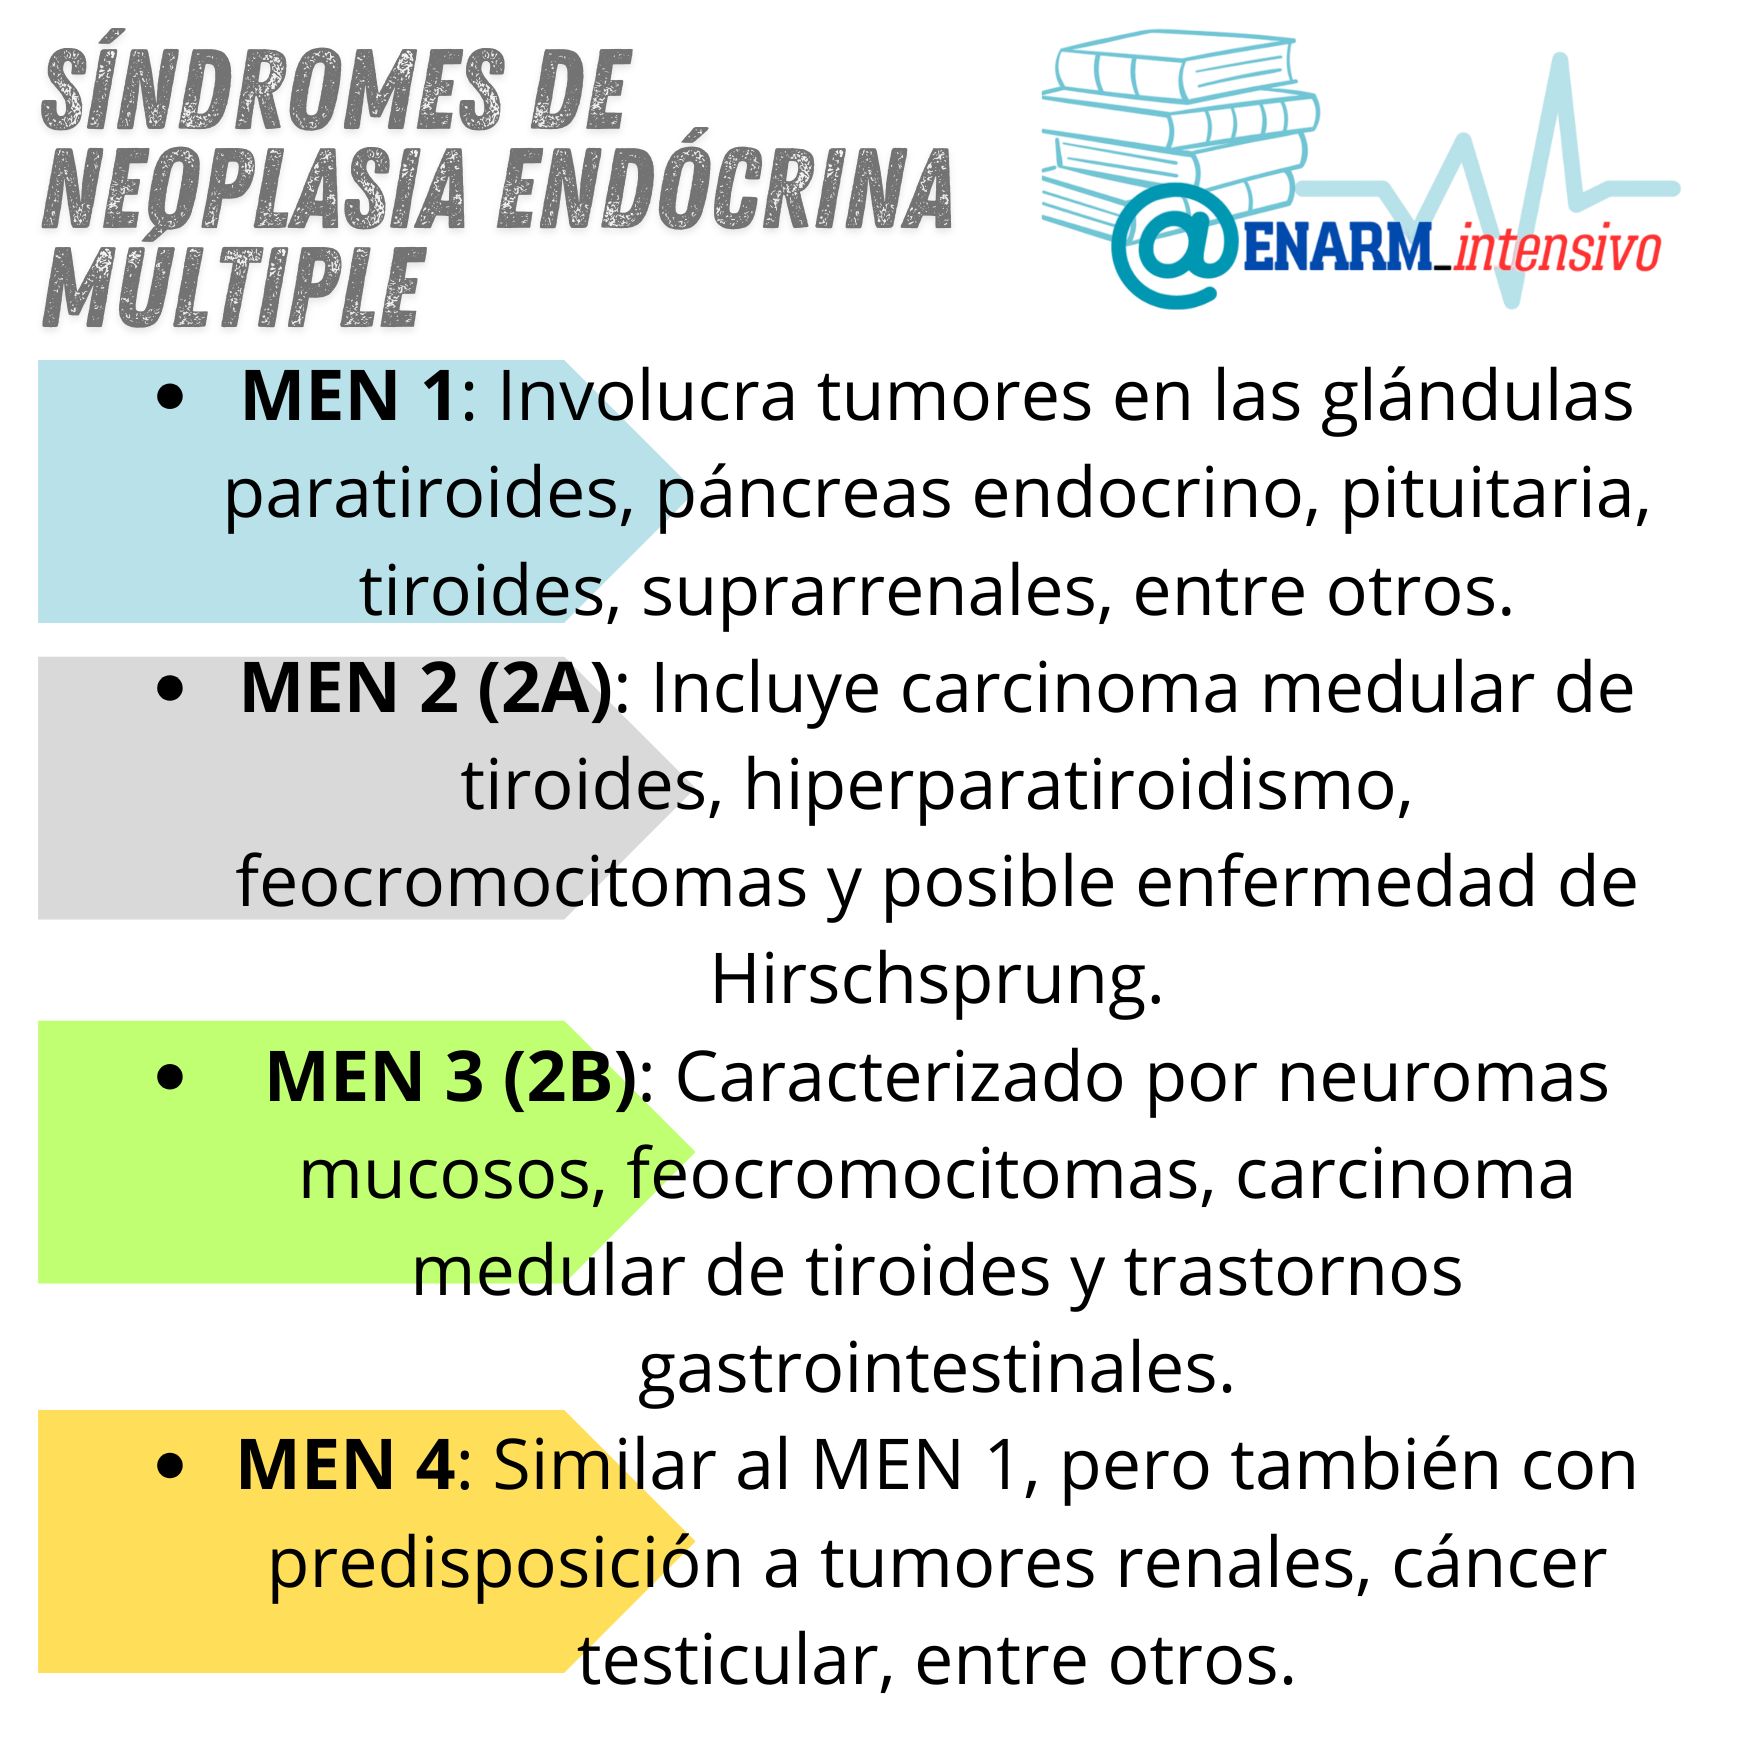

Los síndromes de Neoplasia Endocrina Múltiple (MEN, por sus siglas en inglés) son un grupo de trastornos genéticos que se caracterizan por la predisposición al desarrollo de tumores en dos o más glándulas endocrinas distintas. Estos síndromes se heredan siguiendo un patrón autosómico dominante, lo que significa que basta con una sola copia mutada del gen para que una persona se vea afectada por la enfermedad. La herencia autosómica dominante implica que cualquier individuo que posea una mutación en un gen específico tiene un 50% de probabilidad de transmitir esa mutación a su descendencia, independientemente del sexo del portador.

MEM 1

MEM 2

MEM 3

MEM 4